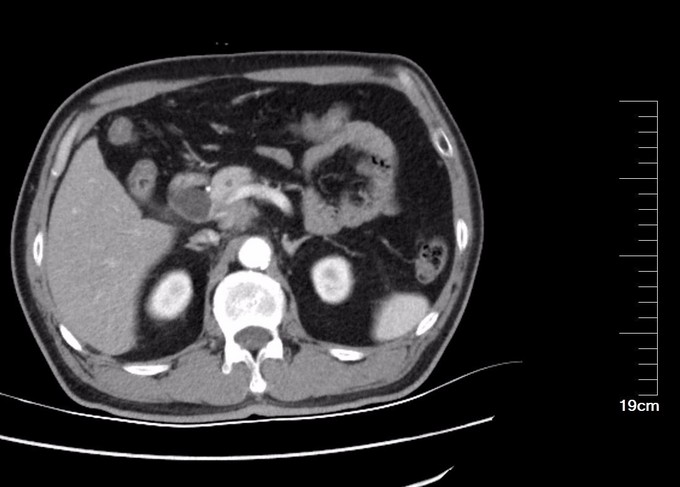

查体:全身皮肤及巩膜黄染,腹部膨隆,无胃肠型,腹软,中上腹压痛,无反跳痛,肝脾未触及,肝肾区无叩痛,肠鸣音6次/分,移动性浊音(-)。 辅查: CT:胰头部隐约见弱强化灶,局部门脉管径变细,胰头周围及腹膜后见增大淋巴结。胆总管胰腺段管壁增厚,明显强化,近端肝内外胆管扩张。胰管未见扩张。胰尾部见小囊状不强化灶,长径约8mm。MR 肝脏表面光滑,各叶比例协调,肝实质信号欠均匀。肝内外胆管普遍扩张,胆总管下段狭窄,中上段扩张,最宽处约1.8cm,胆囊壁增厚,其内信号不均。胰头部见稍长T1稍长T2信号影,境界模糊,范围约2.9cm×1.5cm,胰腺体尾部见长T1长T2信号结节影,大小约8mm×3mm,胰管轻度扩张。脾脏不大。 MRCP:肝内外胆管普遍扩张,胆总管下段狭窄,中上段扩张,宽约1.8cm,胆囊轮廓不清。胰腺体尾部见长T2信号结节影,大小约8mm×3mm,胰管扩张,胰腺头部主胰管狭窄。血清胆红素190.1umol/L,以直接胆红素升高为主。

诊断: 胰头占位 恶性可能大 治疗:全麻下手术探查:肝脏於胆改变,无转移结节,腹壁及盆腔未见癌转移,胰头略增大,切开kocher筋膜,游离十二指肠降段,显露胰头后方,触及胰腺钩突2.5×2.0cm质硬肿物,界不清,胆囊无明显增大,约7×4×3cm,肝总管、胆总管全程明显扩张,直径约1.8cm,术中诊断胰腺头部占位,行胰十二指肠切除术,术中冰冻病理及术后病理证实恶性。病理镜下:癌细胞呈不规则腺样,筛网状排列,部分区域见淋巴组织。胰腺腺癌,高分化,肿物周围见少许淋巴结结构,考虑淋巴结受侵及,胃、肠、网膜未见癌,慢性胆囊炎。CD34及D2-40染色未见明显脉管癌栓,S-100染色见神经侵犯。